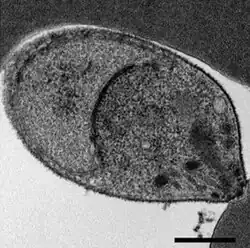

Malaria is traditionally diagnosed by examining Giemsa-stained blood films under a microscope; however, differentiating P. knowlesi from other Plasmodium species in this way is challenging due to their similar appearance.[11] P. knowlesi ring-stage parasites stained with Giemsa resemble P. falciparum ring stages, appearing as a circle with one or two dark dots of chromatin.[18] Older trophozoites appear more dispersed, forming a rectangular-shape spread across the host cell called a "band-form" that resembles the similar stage in P. malariae.[18] During this stage, dots sometimes appear across the host red blood cell, called "Sinton and Mulligans' stippling".[18] Schizonts appear, similarly to other Plasmodium species, as clusters of purple merozoites surrounding a central dark-colored pigment.[18]